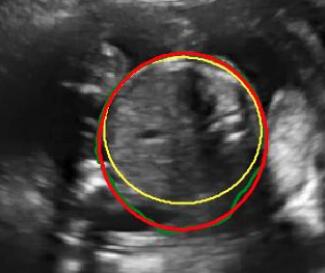

We integrate our shadow confidence maps into an automatic biometric measurement approach [32], and show the biometric measurement performance (measured by DICE) before and after adding shadow confidence maps.

Similar to the ultrasound standard plane classification, shadow confidence maps are integrated into a biometric estimation model described in [32] as an extral channel. Specifically, we train and test four fully convolutional networks with the same hyper-parameters as detailed in [32], and use the same ellipse fitting algorithm described therein. The first network is trained only on the image data used in [32]. The other three networks are trained with an additional input channel for shadow confidence maps that are separately generated by the baseline, the proposed, and the proposedAG method.

We show three examples that are affected by shadows, and show their biometric measurement results in Table V. From this experiment, we find that biometric measurement performance is boosted by up to for problematic failure cases after adding shadow confidence maps. The average performance on the entire test data set stays almost the same since only a small proportion of the test images are affected by strong shadows, mainly because of the image acquisition by highly skilled sonographers.

-H Examples for Biometric Measurement

We visualize the biometric measurement of the three examples shown in Table V. Fig. 16 demonstrates that, for the cases affected by shadow artifacts, the segmentation performance (“EI_seg DICE”) is improved after adding shadow confidence maps as an extra channel. From the first row to the third row in Fig. 16, these three samples are respectively #1, #2 and #3 samples in Table V.